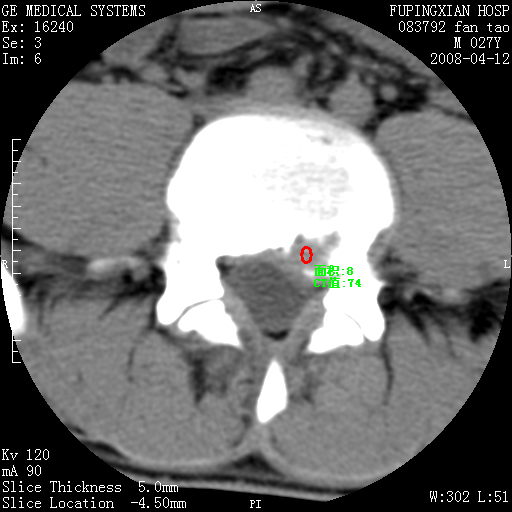

以下是引用前行在2008-4-13 13:53:00的发言:[br]椎间盘髓核终板下突出形成许莫氏结节及椎间盘突出,建议mr检查

以下是引用xclzq_910在2008-4-13 12:43:00的发言:[br]这个应该没什么了,椎间盘突出后反应性骨质吸收硬化.建议mr